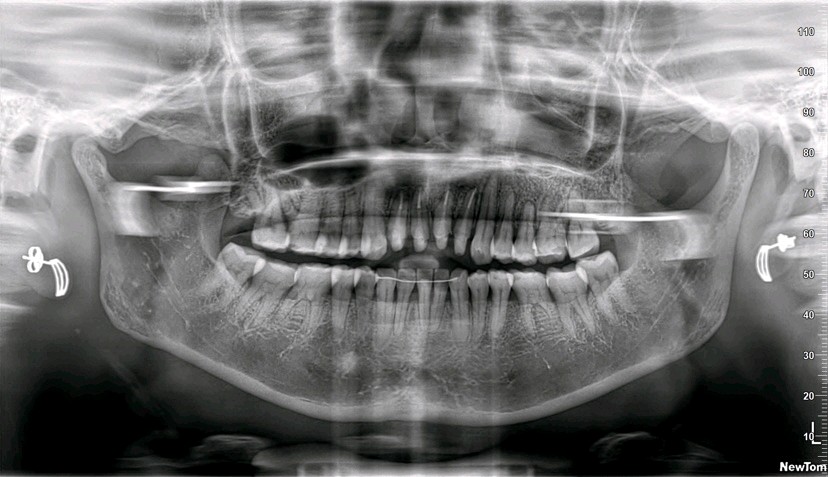

患者女,三十岁,11、12、21,22牙已行根管治疗+烤瓷全冠修复。由于长时间烤瓷牙的佩戴,导致牙龈边缘发黑,边缘不密合,颈缘处牙龈组织出现"黑线"。腭侧部分也出现了崩瓷的现象。对于这种情况,建议患者尽早重新修复,避免二次伤害。患者最终选择重新修复,也给出患者合理的方案,患者选全瓷冠修复,与今日佩戴完毕。边缘密合度良好,形态色泽自然美观,患者满意。

术后